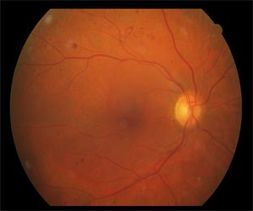

1-Zemin diyabetik retinopati: Ağ tabaa damarlarının tıkanması ve duvarlarının bozulması ile küçük damar genişlemeleri, kan elemanlarının retinaya sızması ile küçük retina içi kanamalar, sert eksuda adı verilen sarı birikintiler görülür.

2-Makülapati: Zamanla maküla bölgesi damarları etkilenince,bu bölgedei damarların zedelenmesi ile beslenme bozukluğu, sıvı sızmadı ödem(ödem) ve bu bölgeye yerleşen kanama ve eksudalar görmeyi etiler.Hasta bulanık ve az görmeden yaınmaya başlar.

3-Proliferatif Diyabetik Retinopati: İstenmeyen yerlerde yeni damarlar gelişir. Bu yeni damarlar göz içine yoğun anamaya, etraflarında gelişen ve gözün içini dolduran yumurta akı kıvamındaki jele(vitreus) doğru uzanan bantaların yaptığı çekinti ile retinanın yerinden kabarmasına(dekolman) sebebiyet verir. Bu gelişmeler ise körlüklesonuçlanır.